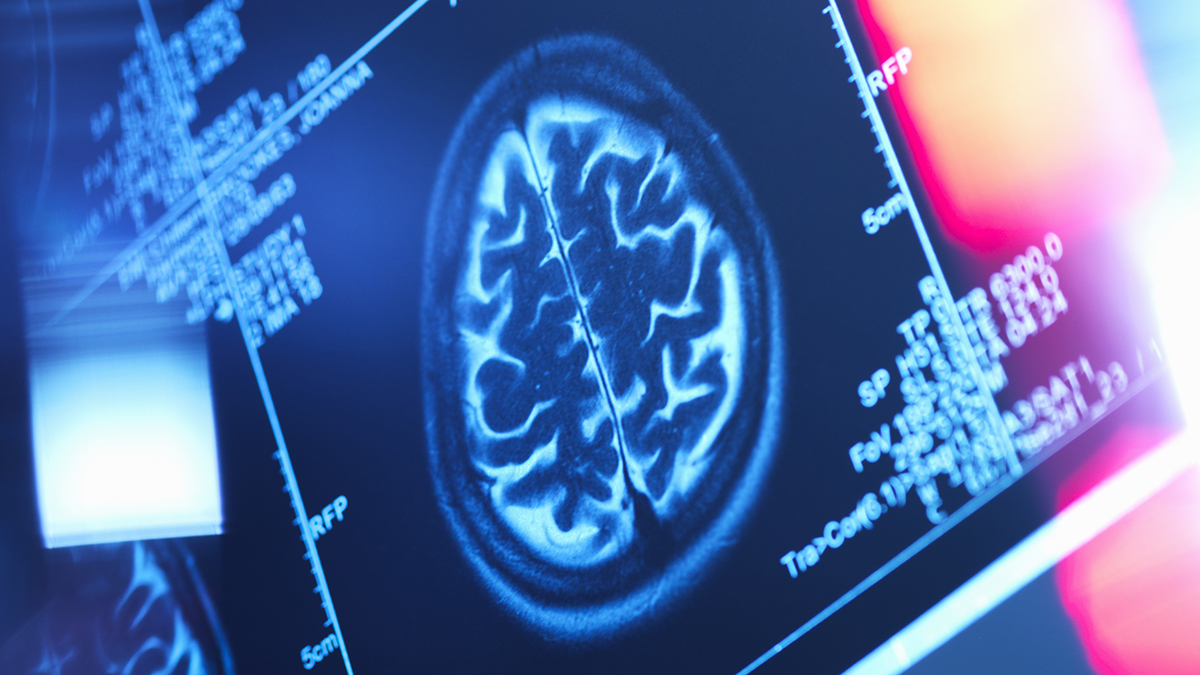

Researchers from Xuzhou Medical University in China analyzed MRI scans of 25,997 individuals from a UK health database, with an average age of 55.

Employing a statistical approach known as latent profile analysis, the research team categorized participants into six groups based on their body fat distribution patterns. They then examined the relationship between these patterns and the individuals’ brain scans and cognitive test outcomes.

Findings revealed that, in comparison to the leanest participants, all five other groups exhibited reduced brain volumes and less gray matter, even those with less body fat than the average person.